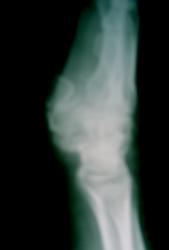

Валентин Львович! Простите, но что Вас смущает в данной картине? Консолидирующийся вколоченный перелом луча в типичном месте. Стояние отломков удовлетворительное. Консолидирующийся перелом ладьевидной кости. Стояние отломков тоже удовлетворительное.

1. Просто было странно, что перед наложением гипсовой повязки хирургами не был вправлен подвывих (вывих) в 1 пястно-запястном суставе, с которым больная добросовестно отходила в "гипсе".

Извиняюсь за то что вмешиваюсь в вашу беседу, но я бы не стал однозначно оценивать представленные рентгенограммы, так как боковые рентгенограммы выполнены в нестандартной косой (ладонной) укладке, и по ним невозможно оценить угловон соотношение дистального метаэпифиза... А закрадывается подозрение, что имеется угол открытый в тыльную сторону, что, само по себе, не может быть расценено как удовлетворительное соотношение.

Оскольчатый перелом дистального метаэфиза лучевой кости в стадии консолидации по эндостальному типу, с неудовлетворительным соотношением отломков, в виде осевой деформации в тыльную сторону. Но, повторюсь, вывод можно сделать лишь по боковой рентгенограмме в стандартной укладке. Угол между дистальным метаэпифизом и диафизом лучевой кости расчитывается следующим образом: на рентгенограмме в боковой проекции проводиться касательная к суставной поверхности лучевой кости, и определяется угол между перпендикуляром к касательной и осью диафиза, в норме составляет от 5 до 15 градусов в ладонную сторону, угол открытый в тыльную сторону всегда расценивается как неудовлетворительное соотношение отломков.

Неа, ни разу не видел чтоб метаэпифизы вколачивались, ротируюся, Т-образно раскалываются, но не вколачиваются. В данной ситуации, подозреваю, что механизм травмы был таков: падение на ладонь с опорой на тенар/гипотенар. Метаэпифиз именно ротировался в тыл. Мы такие переломы расцениваем исключительно как оскольчатые со смещением (осевой деформацией). В данном случае, конечно, осевая деформация не фатальная, хотя, повторюсь, хотелось бы увидеть боковую рентгенограмму. При более выраженных деформациях может происходить штыкообразная деформация кисти, сдавление карпального канала со всеми вытекающими последствиями. У нас бы, наверняка, предложили бы коррегирующую остеотомию, хотя, соглашусь, необходимо оценить функциональный результат.

По поводу вколоченности в данном конкретном случае: на прямой рентгенограмме, действительно, перелом может быть расценен как вколоченный, но при анализе боковой рентгенограммы видно, что данная "вколоченность" имитируется именно тыльной ротацией дистального метаэпифиза лучевой кости.